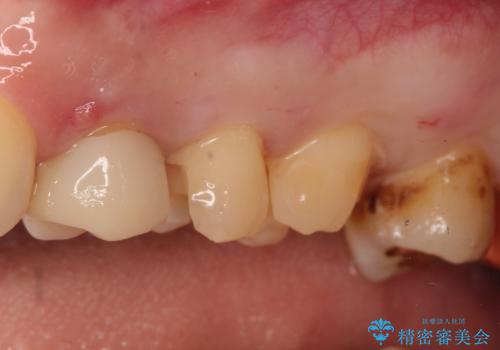

- 定期健診にて虫歯が見つかった患者さんです。他院で保険治療(CR、プラスチック)したところとまだ処置されていないところが虫歯になっていました。

セラミックインレーで治療しました。

以前保険治療で治したところが再び虫歯になっていました。保険治療で使用される材料は主にプラスチックなので必ず劣化がおきます。再治療のリスクを減らすために、セラッミックインレーで治療を行いました。セラミックインレーには劣化がほとんどありません。当院ではシリコンで型取りを行っているので、適合が良い被せものが出来き再治療のリスクを減らすことが出来ます。